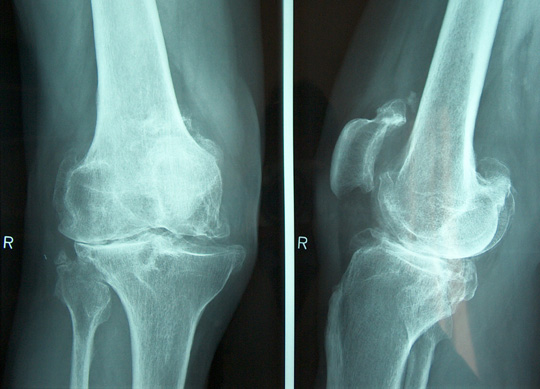

Osteoarthrits of the knee

The knee joint is dived into a medial and lateral compartment.

According to the amount of cartilage loss osteoarthritis may lead to an axial deviation of your leg into varus (O shaped) or into valgus (X-shaped).

A third compartment is between the femur and the patella.

Clinical examination and weight-bearing X ray will determine the diagnosis.